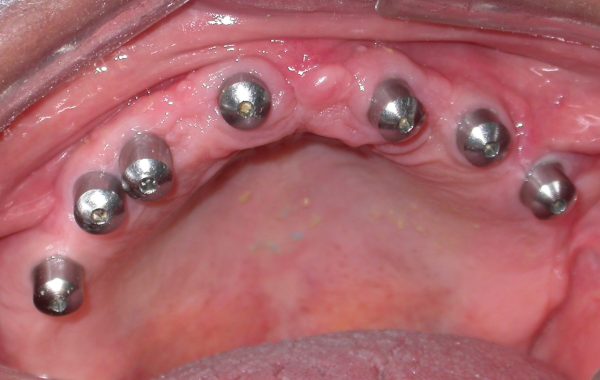

Se le colocaron cuatro implantes para darle mayor retención a la nueva dentadura, además de cinco implantes transicionales con el objetivo de que el paciente pudiera utilizar una dentadura provisional durante el tiempo de oseointegración de los implantes permanentes. El tiempo de oseintegración fue de un mes y medio.

caso 4-2

Despues del mes y medio se colocaron a los cuatro implantes, unos aditamentos retentivos, los cuales le proporcionan a la dentadura mayor retención evitando que se mueva al hablar y al comer.